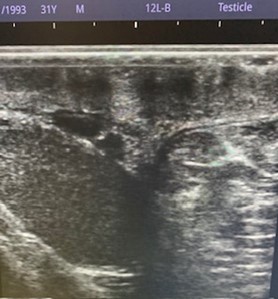

Estudio ecográfico testicular muy accesible sin preparación:

Caso 1: Aumento del volumen escrotal a expensas de la ocupación del hemiescroto izquierdo por grasa mesentérica, sin implicación de asas a través de la OII del canal inguinal (hernia inguinoescrotal izquierda indirecta)